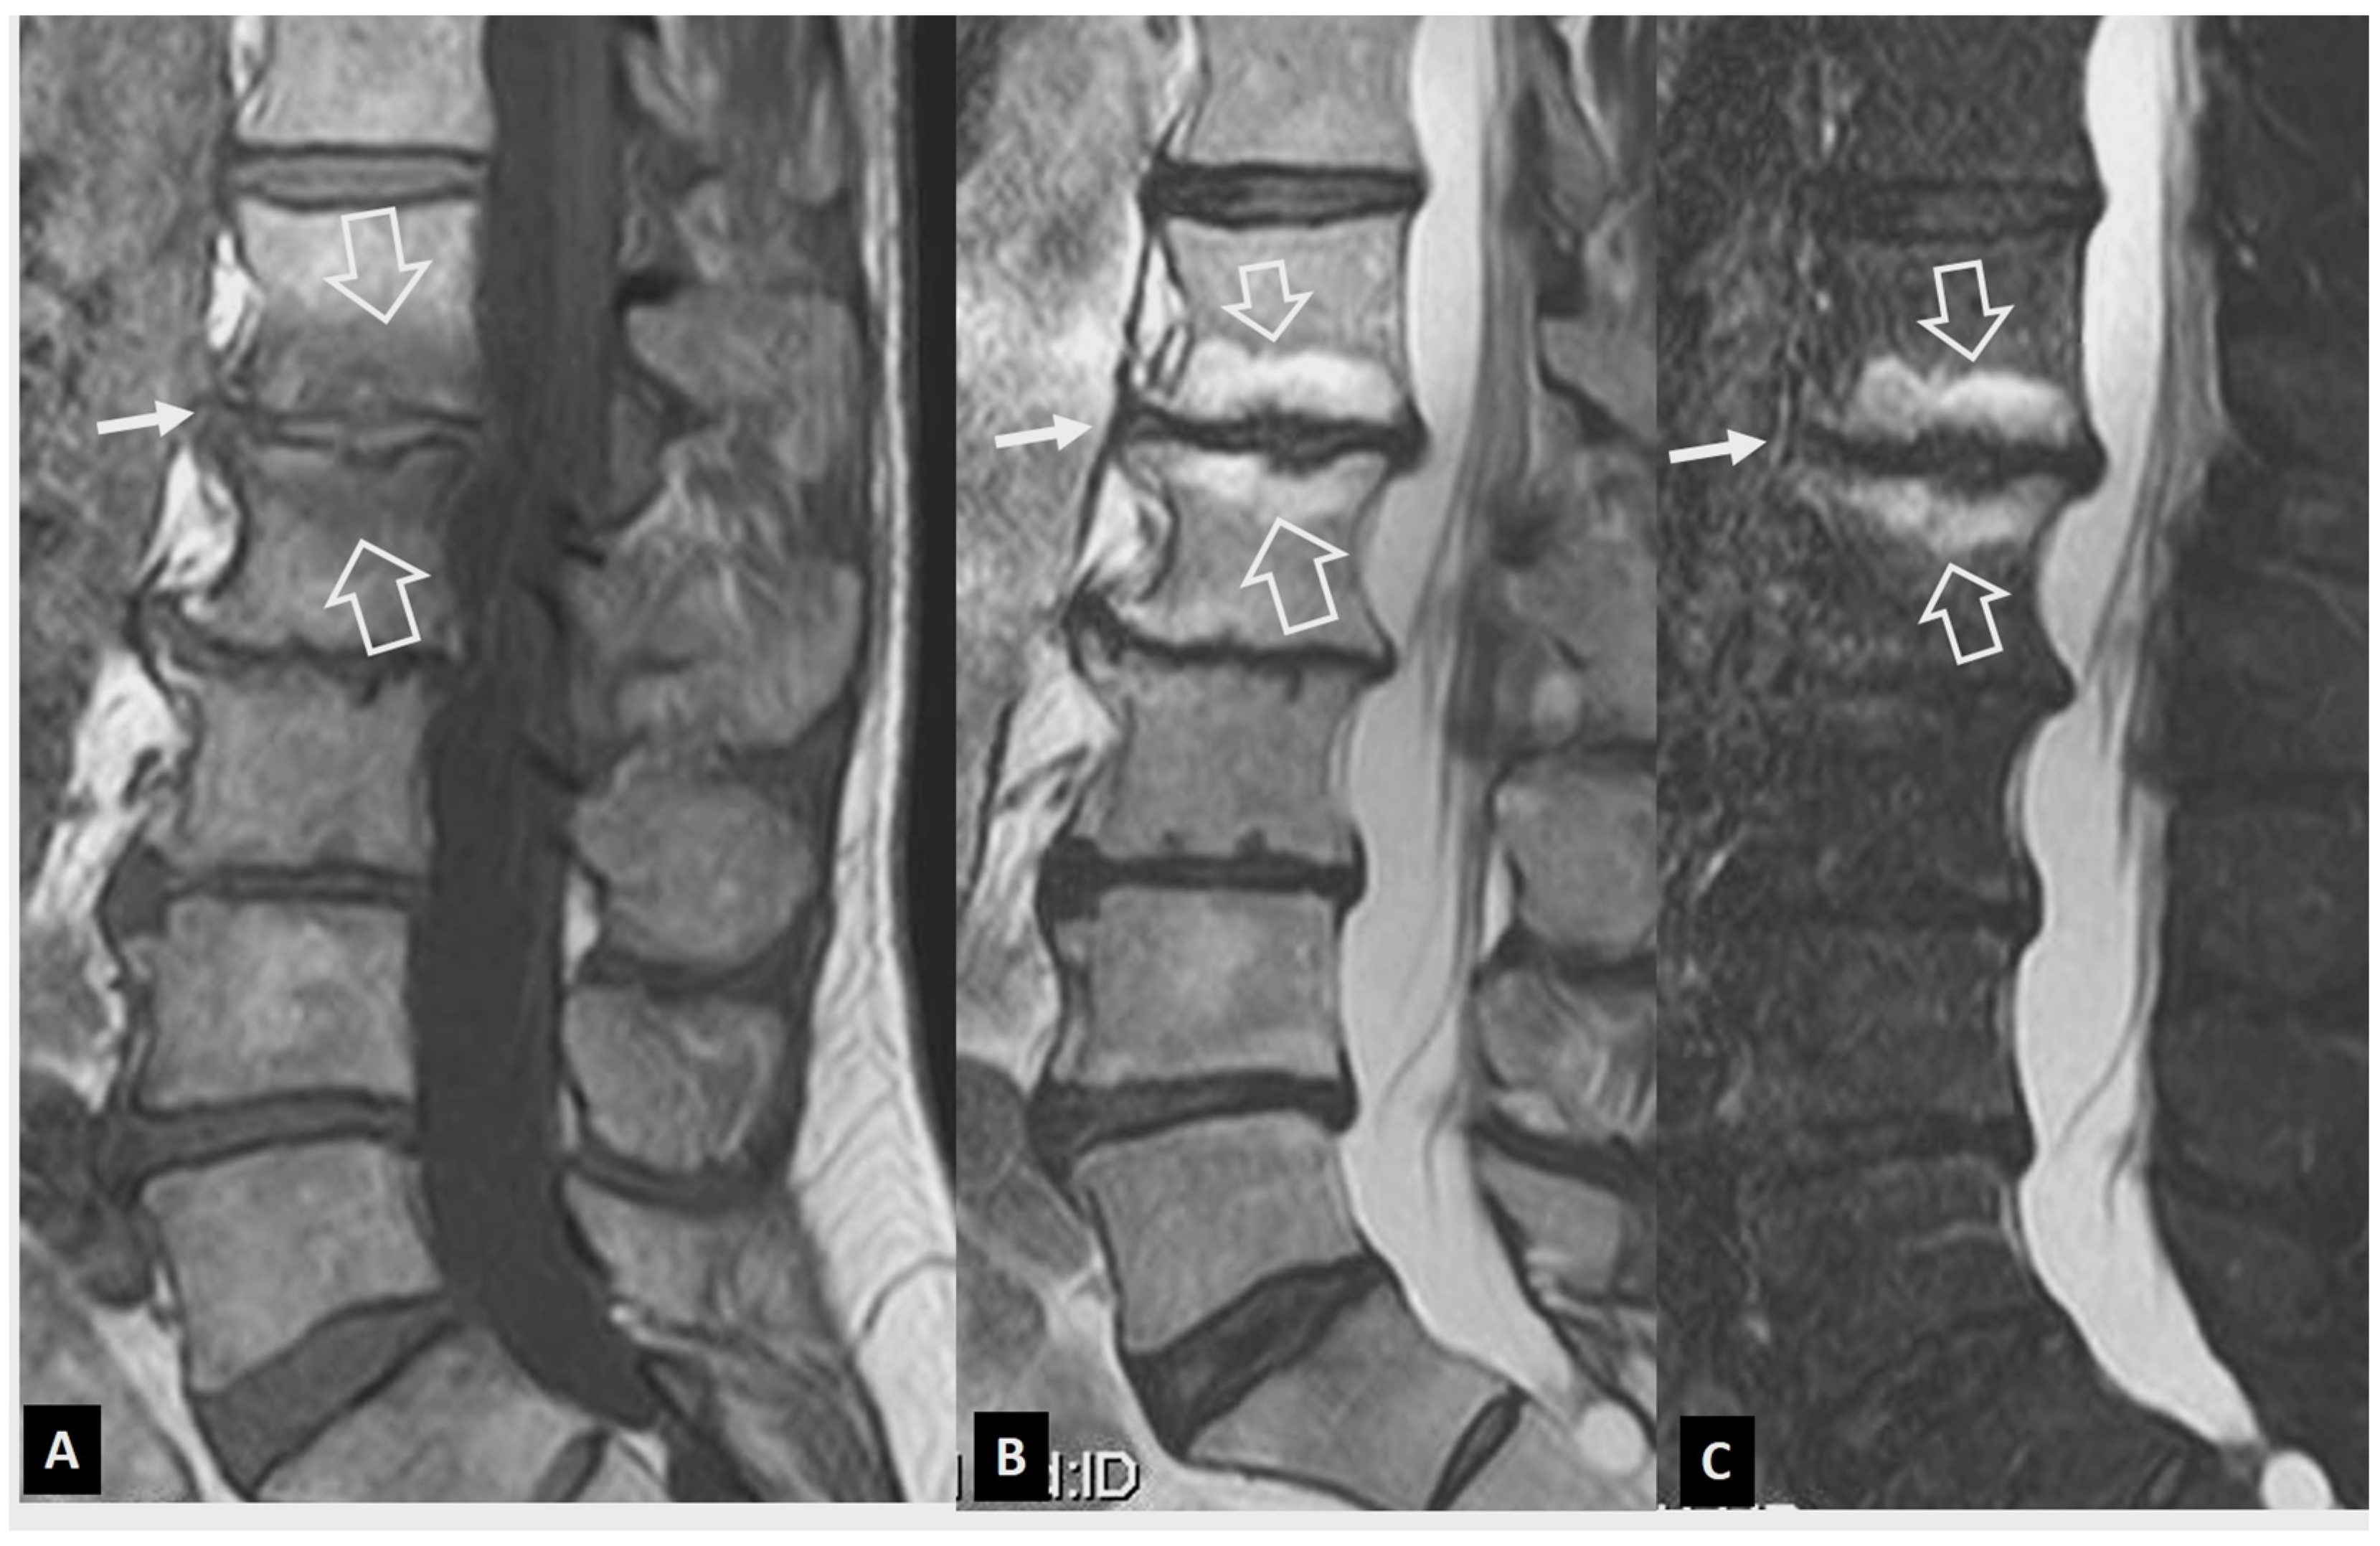

2.1.2. Aseptic Spondylodiscitis

2.1.3. SAPHO Syndrome

2.1.4. Destructive Spondyloarthropathy